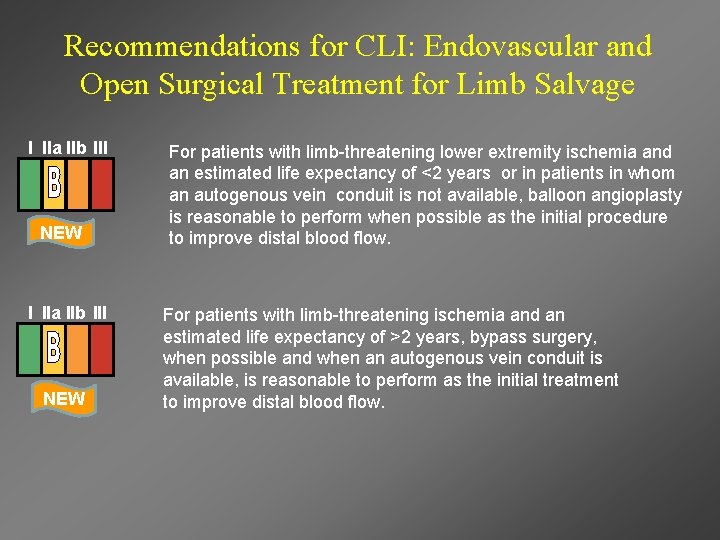

Recommendations for CLI: Endovascular and Open Surgical Treatment for Limb Salvage I IIa IIb III NEW For patients with limb-threatening lower extremity ischemia and an estimated life expectancy of <2 years or in patients in whom an autogenous vein conduit is not available, balloon angioplasty is reasonable to perform when possible as the initial procedure to improve distal blood flow. For patients with limb-threatening ischemia and an estimated life expectancy of >2 years, bypass surgery, when possible and when an autogenous vein conduit is available, is reasonable to perform as the initial treatment to improve distal blood flow.